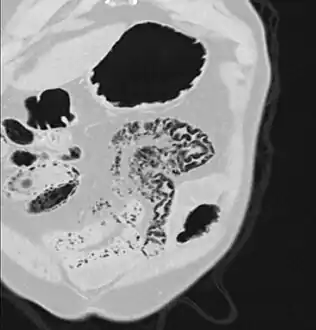

Pneumatosis intestinalis (also called intestinal pneumatosis, pneumatosis cystoides intestinalis, pneumatosis coli, or intramural bowel gas) is pneumatosis of an intestine, that is, gas cysts in the bowel wall.[1][2] As a radiological sign it is highly suggestive for necrotizing enterocolitis. This is in contrast to gas in the intestinal lumen (which is relieved by flatulence). In newborns, pneumatosis intestinalis is considered diagnostic for necrotizing enterocolitis, and the gas is produced by bacteria in the bowel wall.[3] The pathogenesis of pneumatosis intestinalis is poorly understood and is likely multifactorial. PI itself is not a disease, but rather a clinical sign. In some cases, PI is an incidental finding, whereas in others, it portends a life-threatening intra-abdominal condition.

Additional images